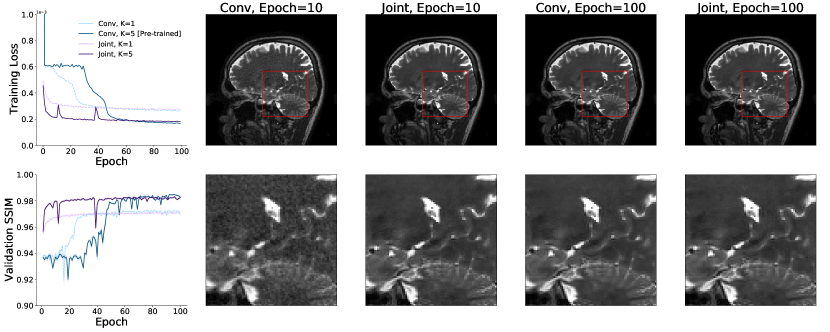

Finally, we evaluate the performance of the proposed joint layers in the setting of an unrolled optimization architecture on real world multicoil MRI data. In this experiment, we replace the image space convolutional layers with our Interleaved layers in the MoDL framework (Aggarwal et al., 2018) for unrolled optimization. We use the authors’ publicly available implementation of MoDL at https://github.com/hkaggarwal/modl. Each iteration of the MoDL network first passes the input through convolutional layers that serve as a data-driven regularizer and then applies an analytical update based on the data consistency term. To keep the total number of convolutions comparable, we train the baseline MoDL network with 10 image convolutional layers in each iteration and the joint MoDL network with 5 Interleaved layers in each iteration. We set iterations for both networks. The authors use the strategy of first training a one-iteration MoDL network and using its weights to initialize the training of a multi-iteration MoDL network. This process speeds up training of the larger unrolled optimization network and avoids instabilities. We found that pre-training of a one-iteration model was unnecessary when using the joint layers, and train both the one-iteration and the five-iteration joint MoDL networks using random initializations. For consistency with the original MoDL training approach, we train all networks using L2 loss.

4.3.1 Results

Figure 10 presents the training curves, validation SSIM, and sample reconstructions for all versions of the MoDL architecture. All networks attain similar validation SSIM values, but MoDL networks with joint layers achieve high reconstruction quality in roughly a third as many epochs as image space networks. Further, using our joint layers removes the need to pretrain a one-iteration network. The five-iteration network with joint layers trains successfully from random initializations. The resulting differences in wall clock training times are summarized in Table 1.

| MoDL Layer | Pre-Training (Hrs) | Training (Hrs) | Total (Hrs) |

| Image Convolution | 19 | 12 | 31 |

| Joint Layer | 0 | 4 | 4 |